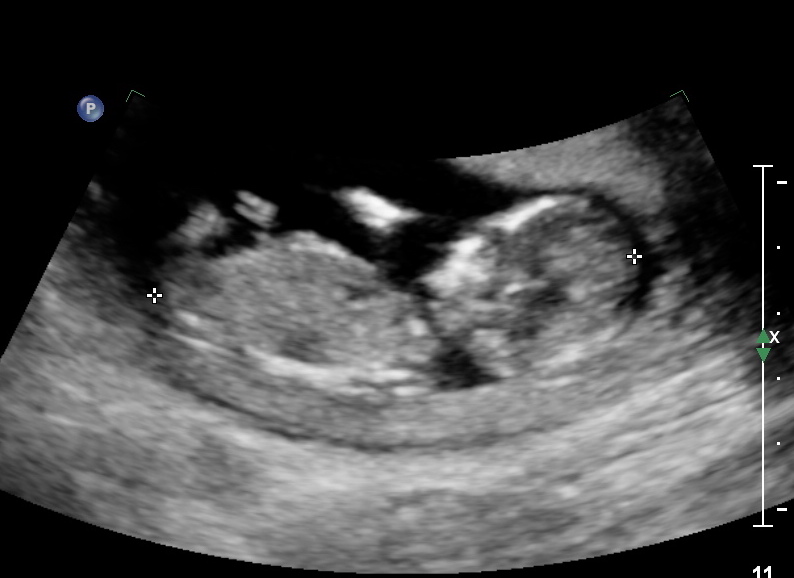

Some shots from today's ultrasound for a possible nub guess! Hopefully these shots are okay for a guess! :)Attachment 37679